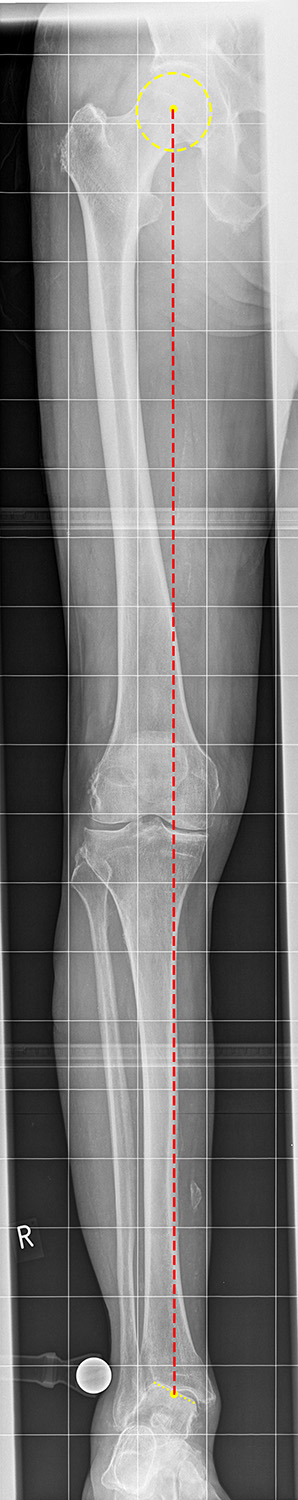

Einbeinstandaufnahme

Kennzeichen des Röntgenbildes:

• Abbildung des gesamten Beins.

• Die Aufnahme ist Basis aller Achskorrekturen.

• Zur Bestimmung der Beinachse wird die Mikulicz-Linie eingezeichnet. Sie verläuft vom Hüftkopfmittelpunkt zur Mitte der Talusrolle.

• Bei einer physiologischen Beinachse verläuft diese Linie durch die Mitte des Kniegelenkes (Eminentia intercondylaris des Tibiaplateaus). Beim Genu varum (O-Bein) verläuft die Mikulicz-Linie medial der Eminentia interconylaris, beim Genu valgum (X-Bein) lateral der der Eminentia interconylaris.

Besondere Bemerkungen zum Beispielbild:

• Valgusarthrose des Sprunggelenks.

• Diskret varische Beinachse bei medial betonter Arthrose des Kniegelenks.

• Lateral des OSG ist eine Eichkugel eingeblendet, die als Referenz bei der Planung von Endoprothesen dient.

• Verkalkung medial in den Weichteilen des Unterschenkels.